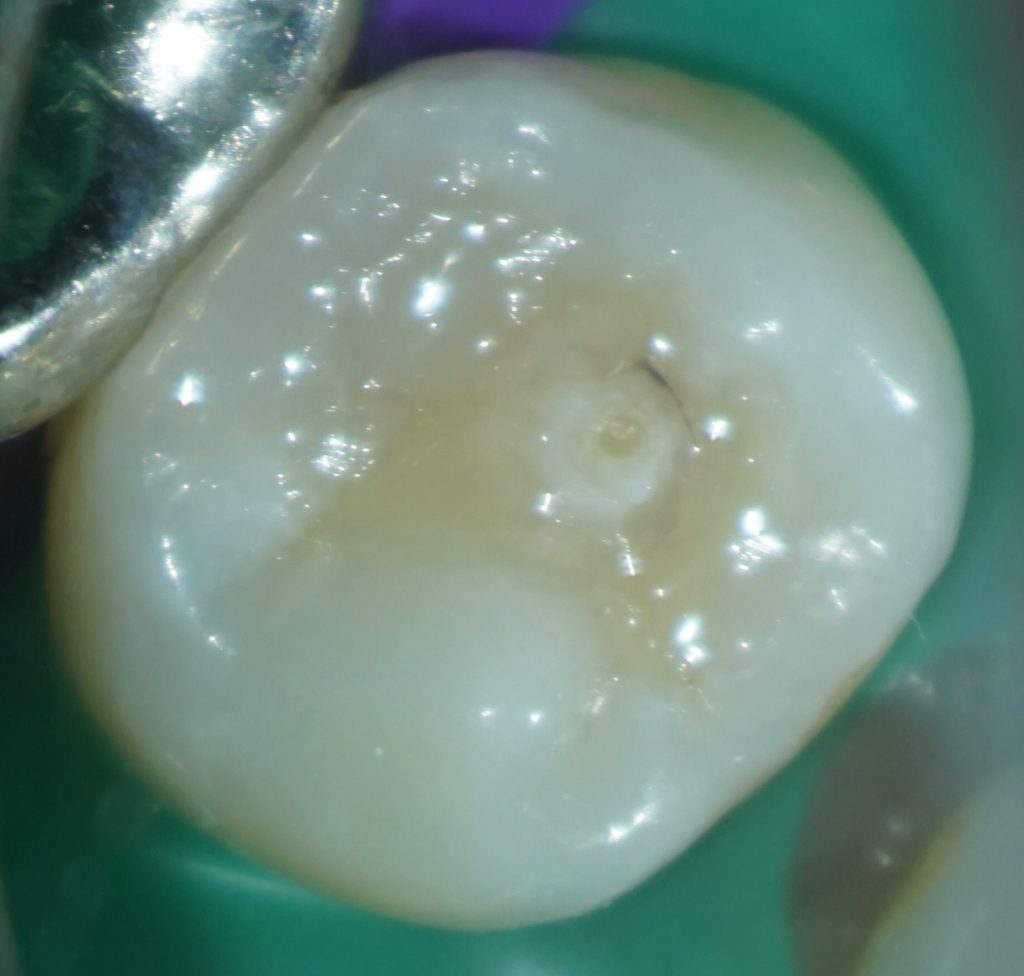

たとえば、この症例はいかがでしょう。

中心結節がある症例では、中心結節に歯髄が嵌入していることが知られています。

この症例を普通に治そうとするとインレーになりますよね。

しかし、通法の形成ではイスムスを形成しているときに露髄してしまうかもしれません。

私はこういった症例の治療をする場合、う蝕を取り除き、

露髄していないことを確認したうえで、コンポジットレジンで修復することがほとんどです。

これを自由診療で行っています。

患者さんは、歯髄を失わなくて済むので自由診療を選択したことをとても喜んでくれます。

少し高額な治療でも、「歯髄を残したい」という患者さんはとても多いと思います。